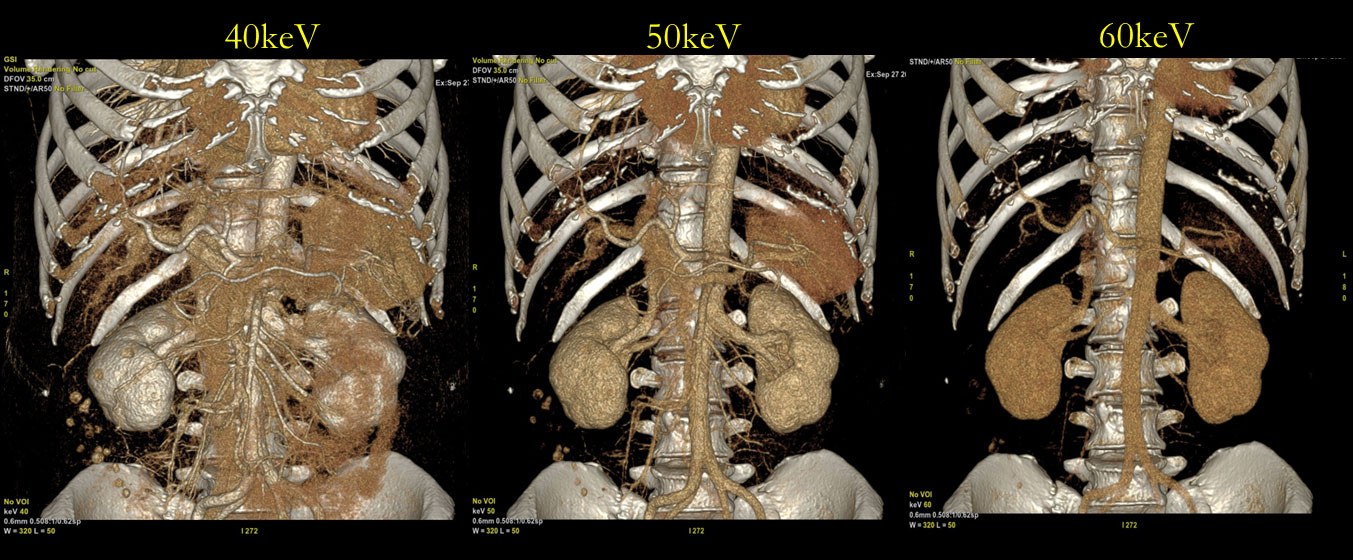

本来ダイナミックCTを行う目的であったが、患者の造影ラインの影響で造影剤の注入が予定より伸びてしまい、十分にCT値が得られなかったことがある。主治医の指示でこの症例(Fig6)はDECTで撮影しており低エネルギー画像を作成することで動脈相のようにVR画像を作成できた症例であった。50keVでは70keVと比べ約2倍、40keVでは70keVと比べ約3倍のCT値を得ることができ、不測の事態でフォローを行うことができた症例である。

RevolutionCT_Minamitohoku07.jpg

Fig6, 造影不良時の低keVにおけるCT値のリカバリー